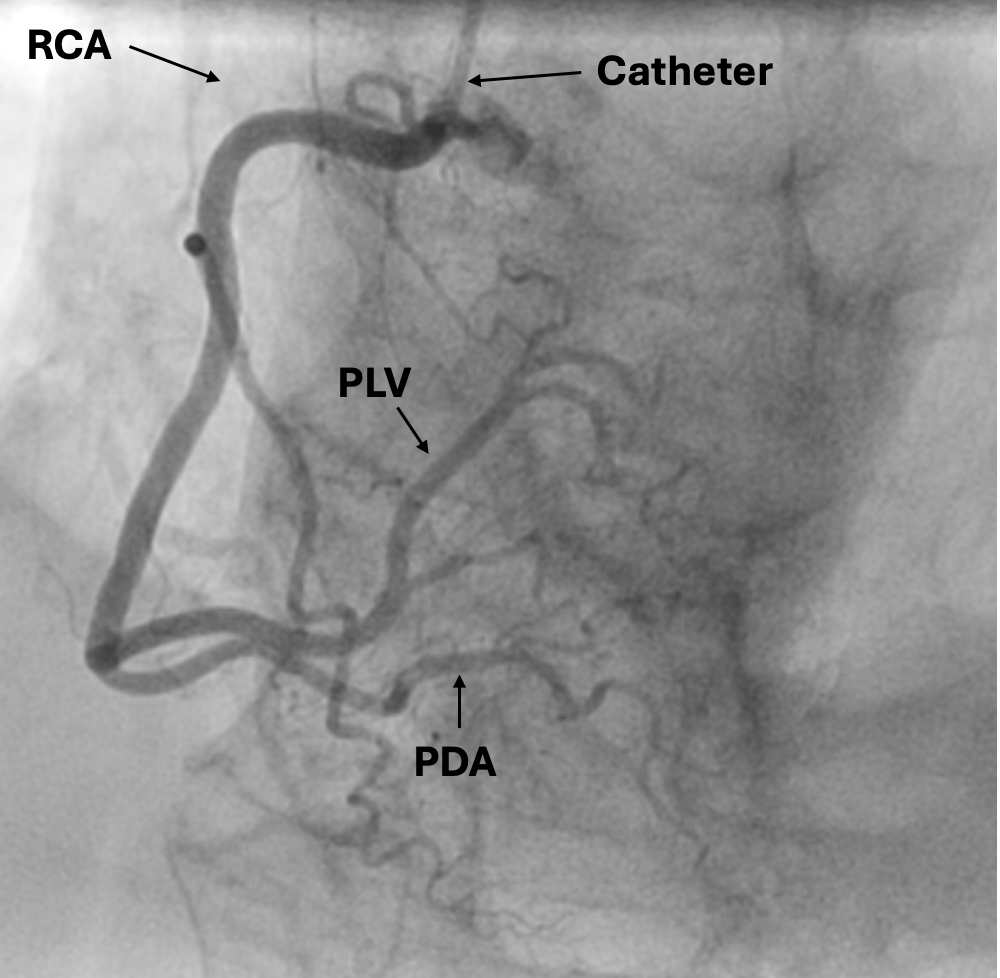

Coronary angio:

RCA: right coronary artery

PLV: posterior left ventricular artery

PDA: posterior descending artery

LAD: left anterior descending artery

Cx: circumflex artery